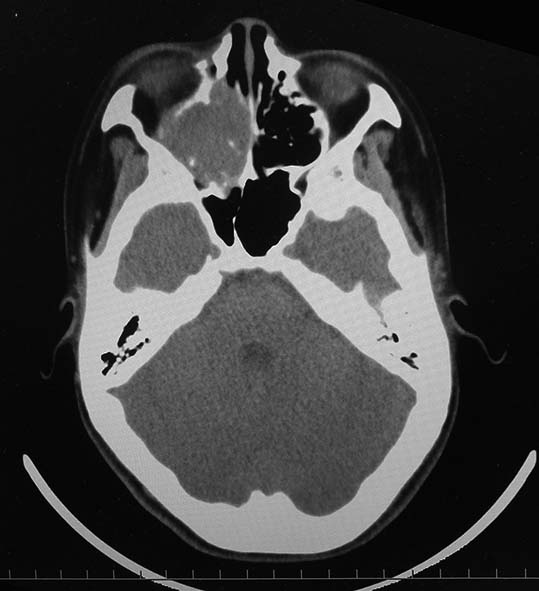

CT所見

副鼻腔腫瘤生検組織